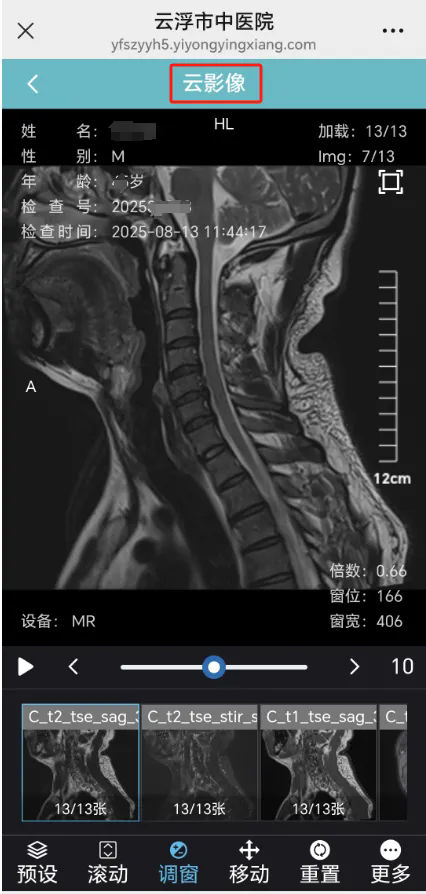

数字影像云影像是指医院在做医学影像学检查时,将患者原始生成的无损压缩DICOM格式图片储存在云端服务器上,之后患者可通过医院提供的二维码查看分享检查报告和原始影像数据的服务。

通俗地说就是没有实体胶片,用手机、Ipad等智能终端就能查看、诊断和分享病人的影像检查资料。

有了云影像,患者不需要携带传统胶片,只要保存自己的二维码,就可以随时查询自己的检查数据和诊断报告,方便复诊、转诊,甚至可以把二维码发送给相关医生会诊,医生只需识别一下二维码就可以查看病人的影像资料,大大降低患者的时间、人力成本。同时,使用云影像还可以为患者节约一部分打印胶片的费用。